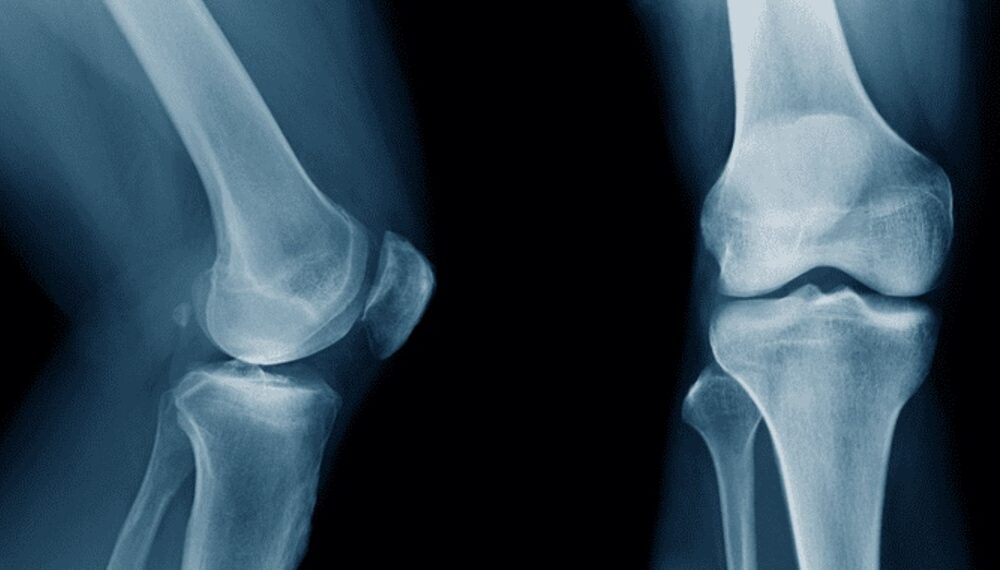

Researchers in China have developed a groundbreaking adhesive called Bone-02, capable of repairing fractures in as little as three minutes. This innovative bio-adhesive, which naturally dissolves...

Researchers in China have developed a groundbreaking bio-adhesive known as Bone-02, which has the potential to transform fracture treatment. This innovative material can repair bone fractures...